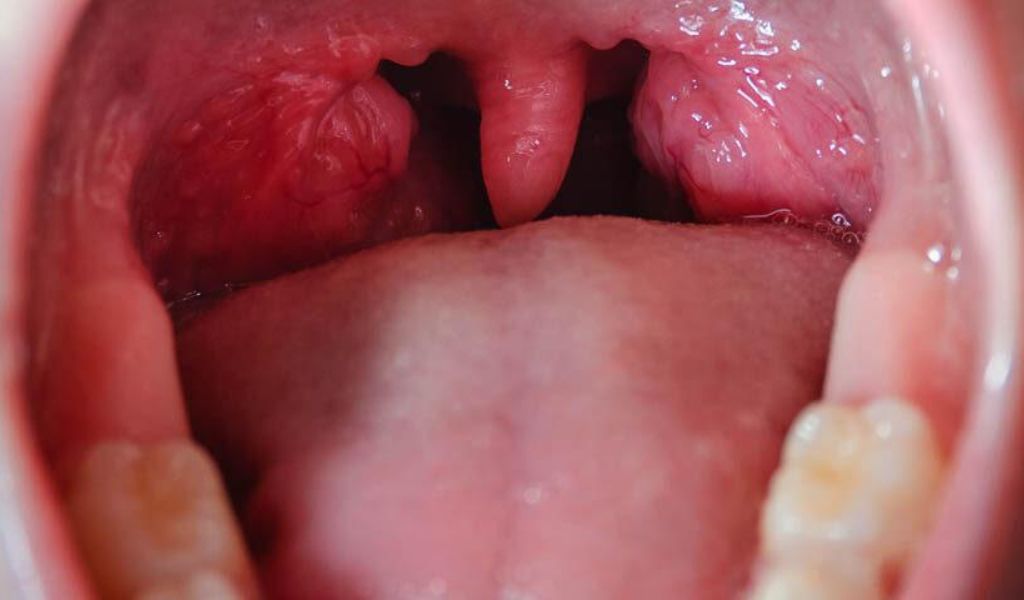

Viêm amidan cấp (viêm họng đỏ)

Viêm amidan cấp thường do virus gây ra, hay gặp ở trẻ em và có xu hướng khởi phát đột ngột. Đây là giai đoạn viêm amidan ban đầu, khi amidan bị viêm rõ ràng nhưng chưa xuất hiện mủ. Đặc điểm của amidan cấp có thể gồm:

- Amidan sưng to, đỏ tươi, bề mặt bóng loáng;

- Không có mủ trắng hay vết loét trên amidan;

- Họng đỏ rực, đôi khi kèm theo lưỡi gà bị lệch.

Ở giai đoạn này, amidan có thể to gấp đôi kích thước bình thường. Nếu không theo dõi và chăm sóc phù hợp, viêm dễ lan sang tai giữa, gây biến chứng viêm tai giữa cấp.